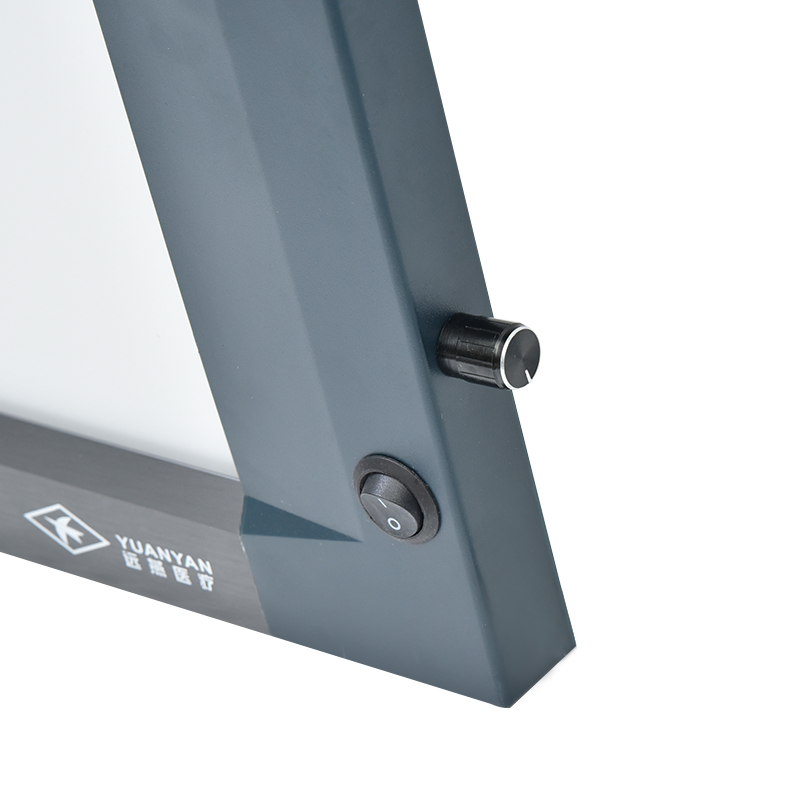

Negatoscopio LED de panel único/doble/triple para películas de rayos X médicos, caja de visualización de películas LED ultradelgada, iluminador de películas LED.

Panel único/doble/triple de LED Negatoscopio médico para películas de rayos X, caja de visualización de películas de LED ultradelgada, iluminador de películas de LED – Comprar visor de películas de negatoscopio médico, visor de películas de negatoscopio, producto de caja de visualización de películas de rayos X